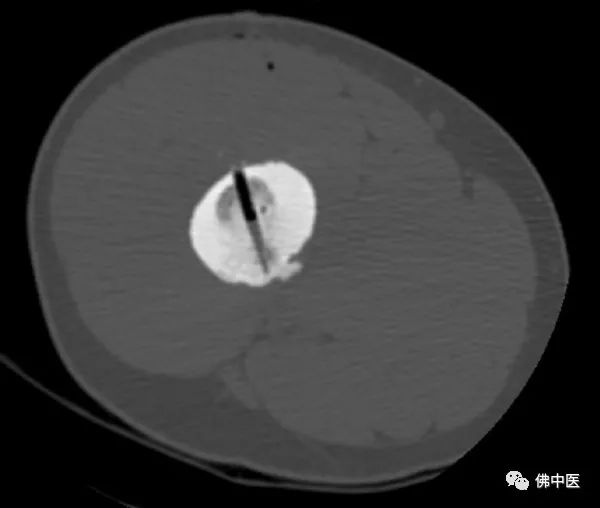

此为横切面图

陈先生左腿股骨病灶

术中,射频针直击病灶